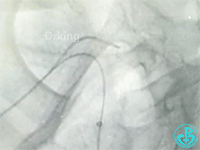

从肱动脉置入8F鞘管,送导丝至“漏口”无法到位,导丝习惯性穿行右胸肩峰动脉中,造影发现血液外溢消失,考虑穿孔口为右胸肩峰动脉远端。接下来送入三个弹簧圈。

最后结果: